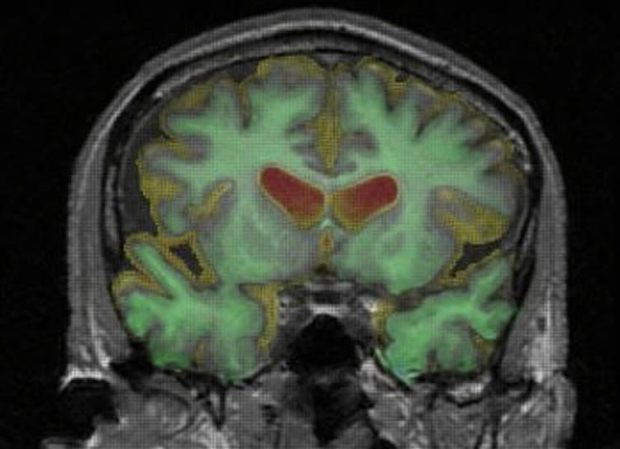

Neuroscientists at the University of Bristol are a step closer to understanding how the connections in our brain which control our episodic memory work in sync to make some memories stronger than others. The findings, published in Nature Neuroscience, reveal a previously unsuspected division of memory function in the pathways between two areas of the brain, and suggest that certain subnetworks within the brain work separately, to enhance the distinctiveness of memories.